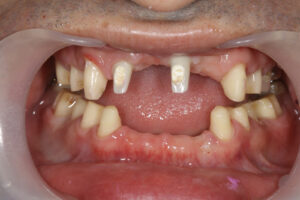

上の前歯が自然に抜けた 40歳男性

H28.12.

大阪市福島区

40歳男性

40歳・男性

初診日 2016. 12.  (5年経過症例)

患者様の症状

1年前から他の歯科医院にて部分的な治療を受けたが、どんどん歯が悪くなって、見た目が良くない・噛めないとのことで再治療を希望された。昨日、上の前歯が自然に取れた、他の医院に行こうとしたところ知人に当医院を勧められ来院した。アングルクラスⅡであった。

治療法

全顎的に歯周病が進行し、ほとんどの歯に動揺が見られた。アングルクラスⅢで下顎前歯部に叢生が見られ、全顎の再生療法の後に、全顎的にオールセラミッククラウンを装着し、既存の被せのやり直しを行なった。

治療結果

審美的な仕上がりで、患者自身も満足した。5年経過し良好である。

現在は2〜3ヶ月おきのメインテナンス中である。